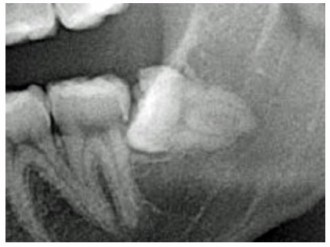

初診時に口腔内の診査やレントゲンで顎骨や歯の状態を検査します。必要に応じてCT検査(X線を用いた断層画像)を行い、顎骨の状態や歯の形および方向や位置、周囲の神経や血管との位置関係等を三次元的に評価した上で抜歯計画を立てています。

パノラマレントゲン画像